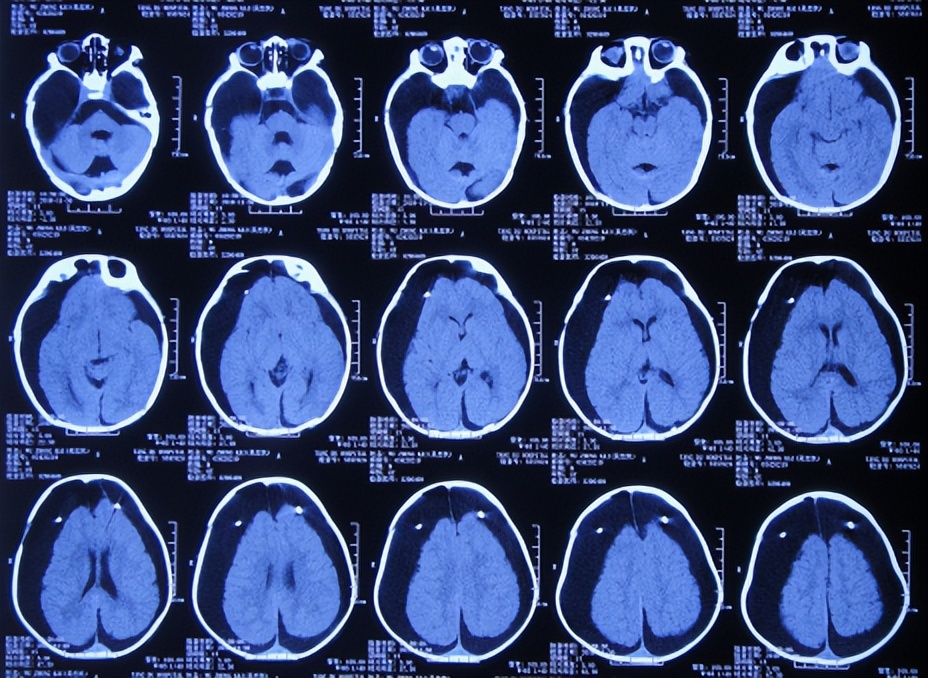

为治疗蛛网膜囊肿、脑积水,于2018年9月13日(发现蛛网膜囊肿后2天),家属带患儿住入第2家医院,湖北省十堰市某三甲医院,查头颅核磁示双颞叶蛛网膜囊肿、脑积水( 图-2 )。

图-2: 2018年9月13日头颅核磁